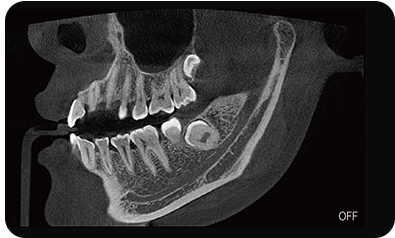

真人正侧位投影,实现CT成像区域无极可调

可根据临床需求任意调整成像区域大小实现局部超清三维显示

临床样片